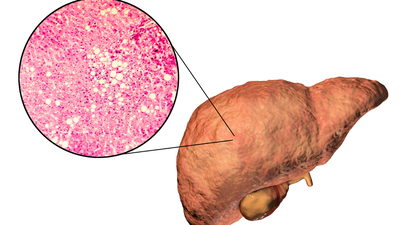

Fatty liver disease is the kind of public health crisis that only a few would be able to escape from. Nearly 38% of adults are now estimated to have Non-Alcoholic Fatty Liver Disease (NAFLD), based on a systematic review published in the Journal of Hepatology.Fatty liver diagnosis, as most of us think, is simply the accumulation of fat in the liver, but to our surprise, it is more than simple fat buildup. Dr. Robert DeBease, a functional medicine expert, says that it’s more complicated than that. In his opinion, a fatty liver issue is more of a matter of what’s going on with the nutrients within your body, and specifically points to copper, vitamin A, and even the sugar in fruit.

First, let’s reconsider the simple concept of fatty liver. Dr. DeBease explains that having this condition isn’t so much about fat. Rather, “hidden triggers,” and these are copper, vitamin A, and fruit sugar (fructose). The liver, is the toxin filtering organ, and its key responsibility is to keep the iron out of the liver and into the blood, thereby keeping the body in motion.This is where it gets confusing. If you don’t have adequate copper or vitamin A, that iron becomes held back in the liver. Visualize the iron as a truckload that can’t depart the warehouse. This inventory begins to destroy liver cells and makes fat start to accumulate. So, in supporting your liver, it’s not merely about consuming less fat—it’s about aiding this iron-shuttling process to function properly.